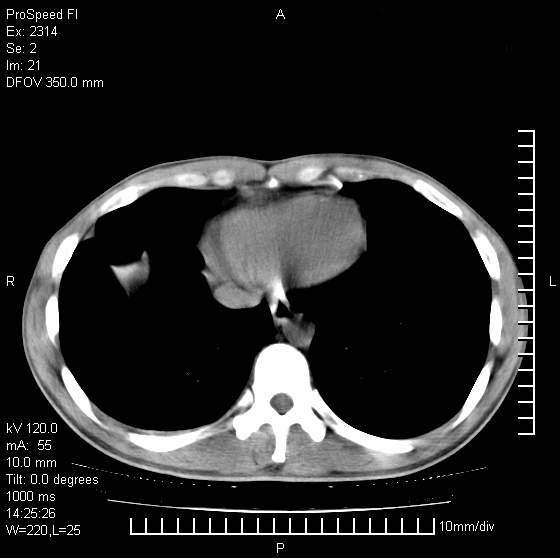

男性,再生障碍性贫血,入院前发热10天,最高40c,右侧胸痛,外院ct示右上,中肺边缘模糊的球性影(就是我现在图中标示的范围),考虑炎症,在我院使用头孢呋辛,洛美沙星10天,高烧消退,自感下午稍有发热,但今天ct示右上,中肺病灶明显扩大,还是考虑炎症,看其中的球型影是否霉菌感染??,是否能排除结核?

考虑肺脓疡

考虑肺脓肿。

支持右肺上叶、中叶外侧段节段性肺炎伴脓肿形成。